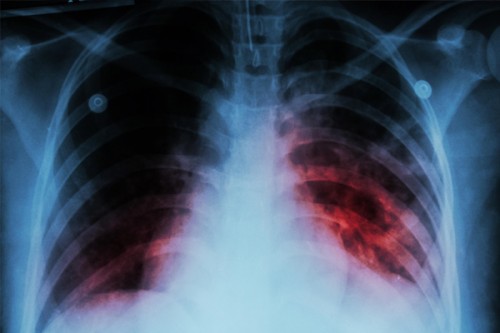

Chennai, Feb 7 (IANS) Tamil Nadu health department has commenced a major drive against Tuberculosis (TB) after 5,000 people were reported dead in the state due to the disease in 2022.

Medical officers of the Tamil Nadu health department warned that patients who are having cough with sputum for a minimum of two weeks with unexplained weight loss or loss of appetite and with blood-stained sputum must test for TB.